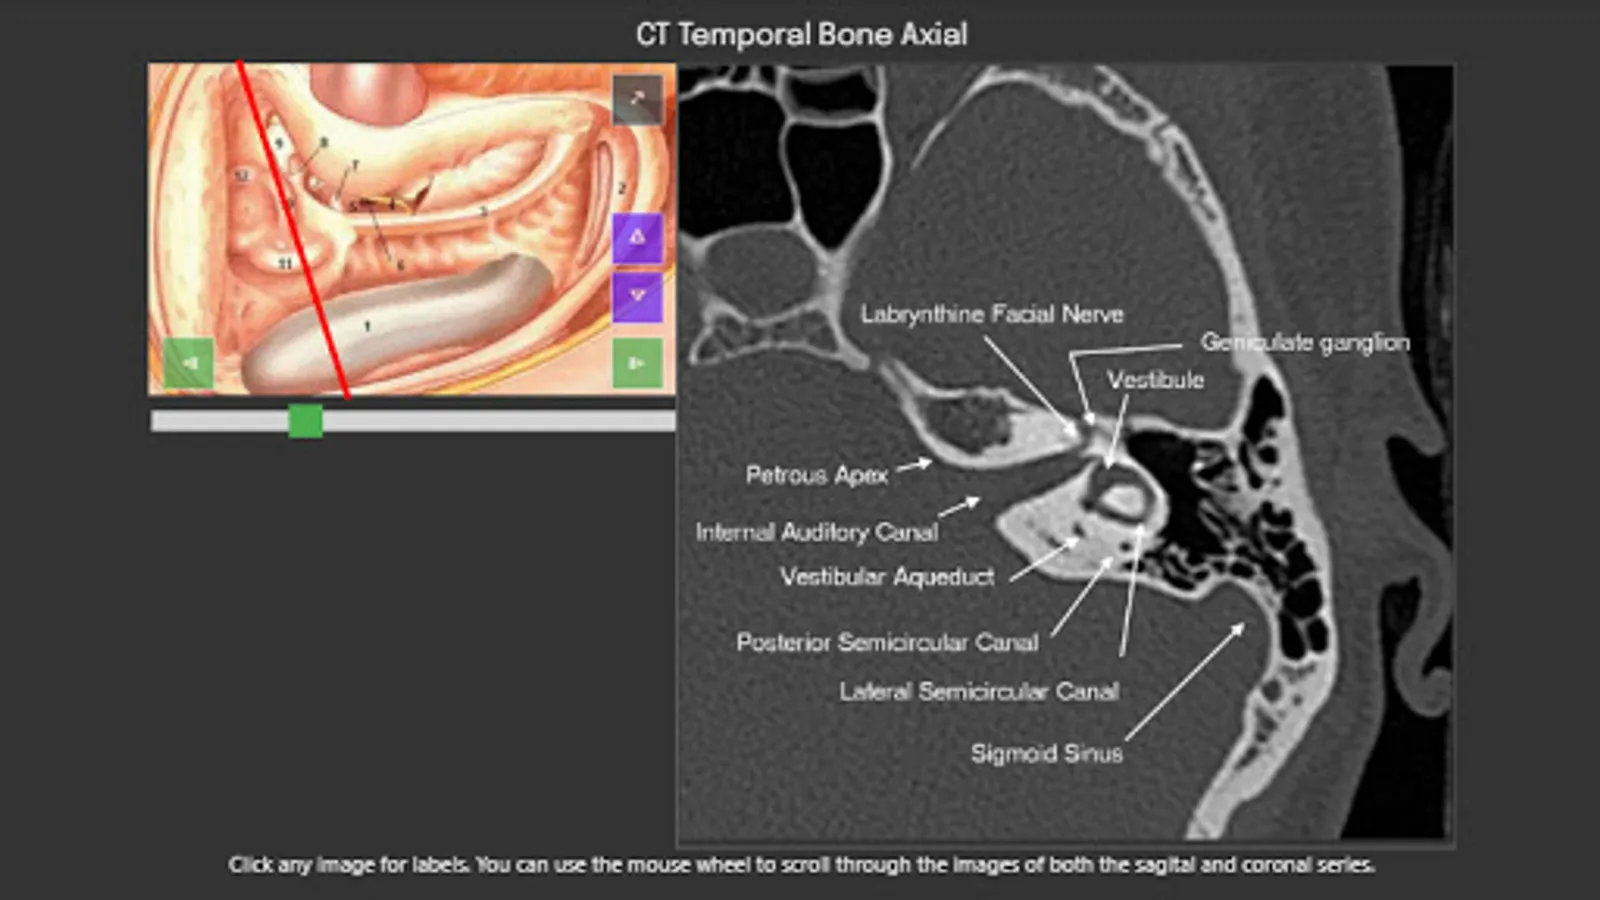

For easy of understanding CT scan anatomy, the content is correlated in two planes, with one serving as a reference. Hence it is much easier to understand the anatomy as we face in the clinical situation. Both the planes can be individually scrolled, so depth is easier to understand.